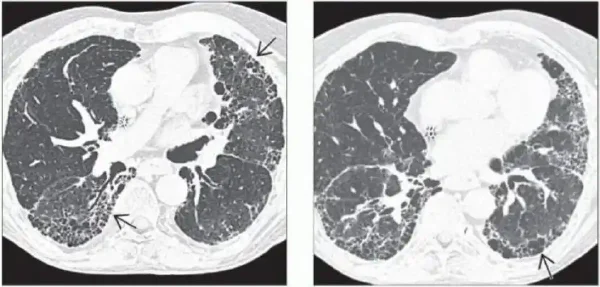

从病理角度来看,矽肺可以表现为肺泡和肺间质的弥漫性纤维化,并且这种纤维化是不可逆的。影像学上,矽肺常常表现为双肺多发结节、网状影和肺门淋巴结钙化等特征性改变。

根据临床症状,矽肺的分类还可以包括有症状的矽肺和无症状的矽肺。无症状矽肺在早期可能通过X线或CT扫描发现,而有症状的矽肺则表现为持续咳嗽、呼吸困难、胸痛等症状。值得注意的是,即使在无症状阶段,矽肺仍然持续进行,导致肺功能不可逆的损害。

影像学检查是确诊矽肺的重要手段。标准的胸部X线片和高分辨率CT扫描是常用的方法,这些影像学手段能够清晰显示肺部的纤维化和结节等特征性改变。

中期矽肺通常表现为明显的影像学改变,如多发结节、网状影及肺间质明显纤维化。此时患者可能出现轻度至中度的呼吸困难、段落性的干咳等症状,肺功能测试结果显示中度损害。

晚期矽肺是疾病发展的最终阶段,影像学检查显示广泛的肺纤维化和巨结节,肺功能严重受损。患者常常出现重度呼吸困难、持续咳嗽和并发症如肺心病、呼吸衰竭等。